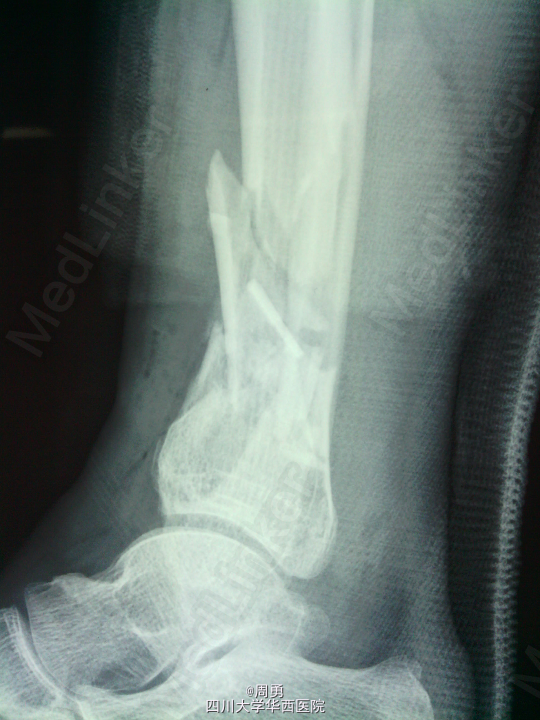

闭合穿针复位腓骨在开放性骨折中应用和意义

某些腓骨骨折常无需处理,但在开放性骨折一期处理创面同时,为了达到恢复肢体长度、条件允许情况下最大可能复位骨折、简化二期手术目的,某些时候复位腓骨并闭合穿克氏针对骨折复位和固定会有一定帮助,选几年前2个博士住院总期间X片示意,欢迎大家交流。